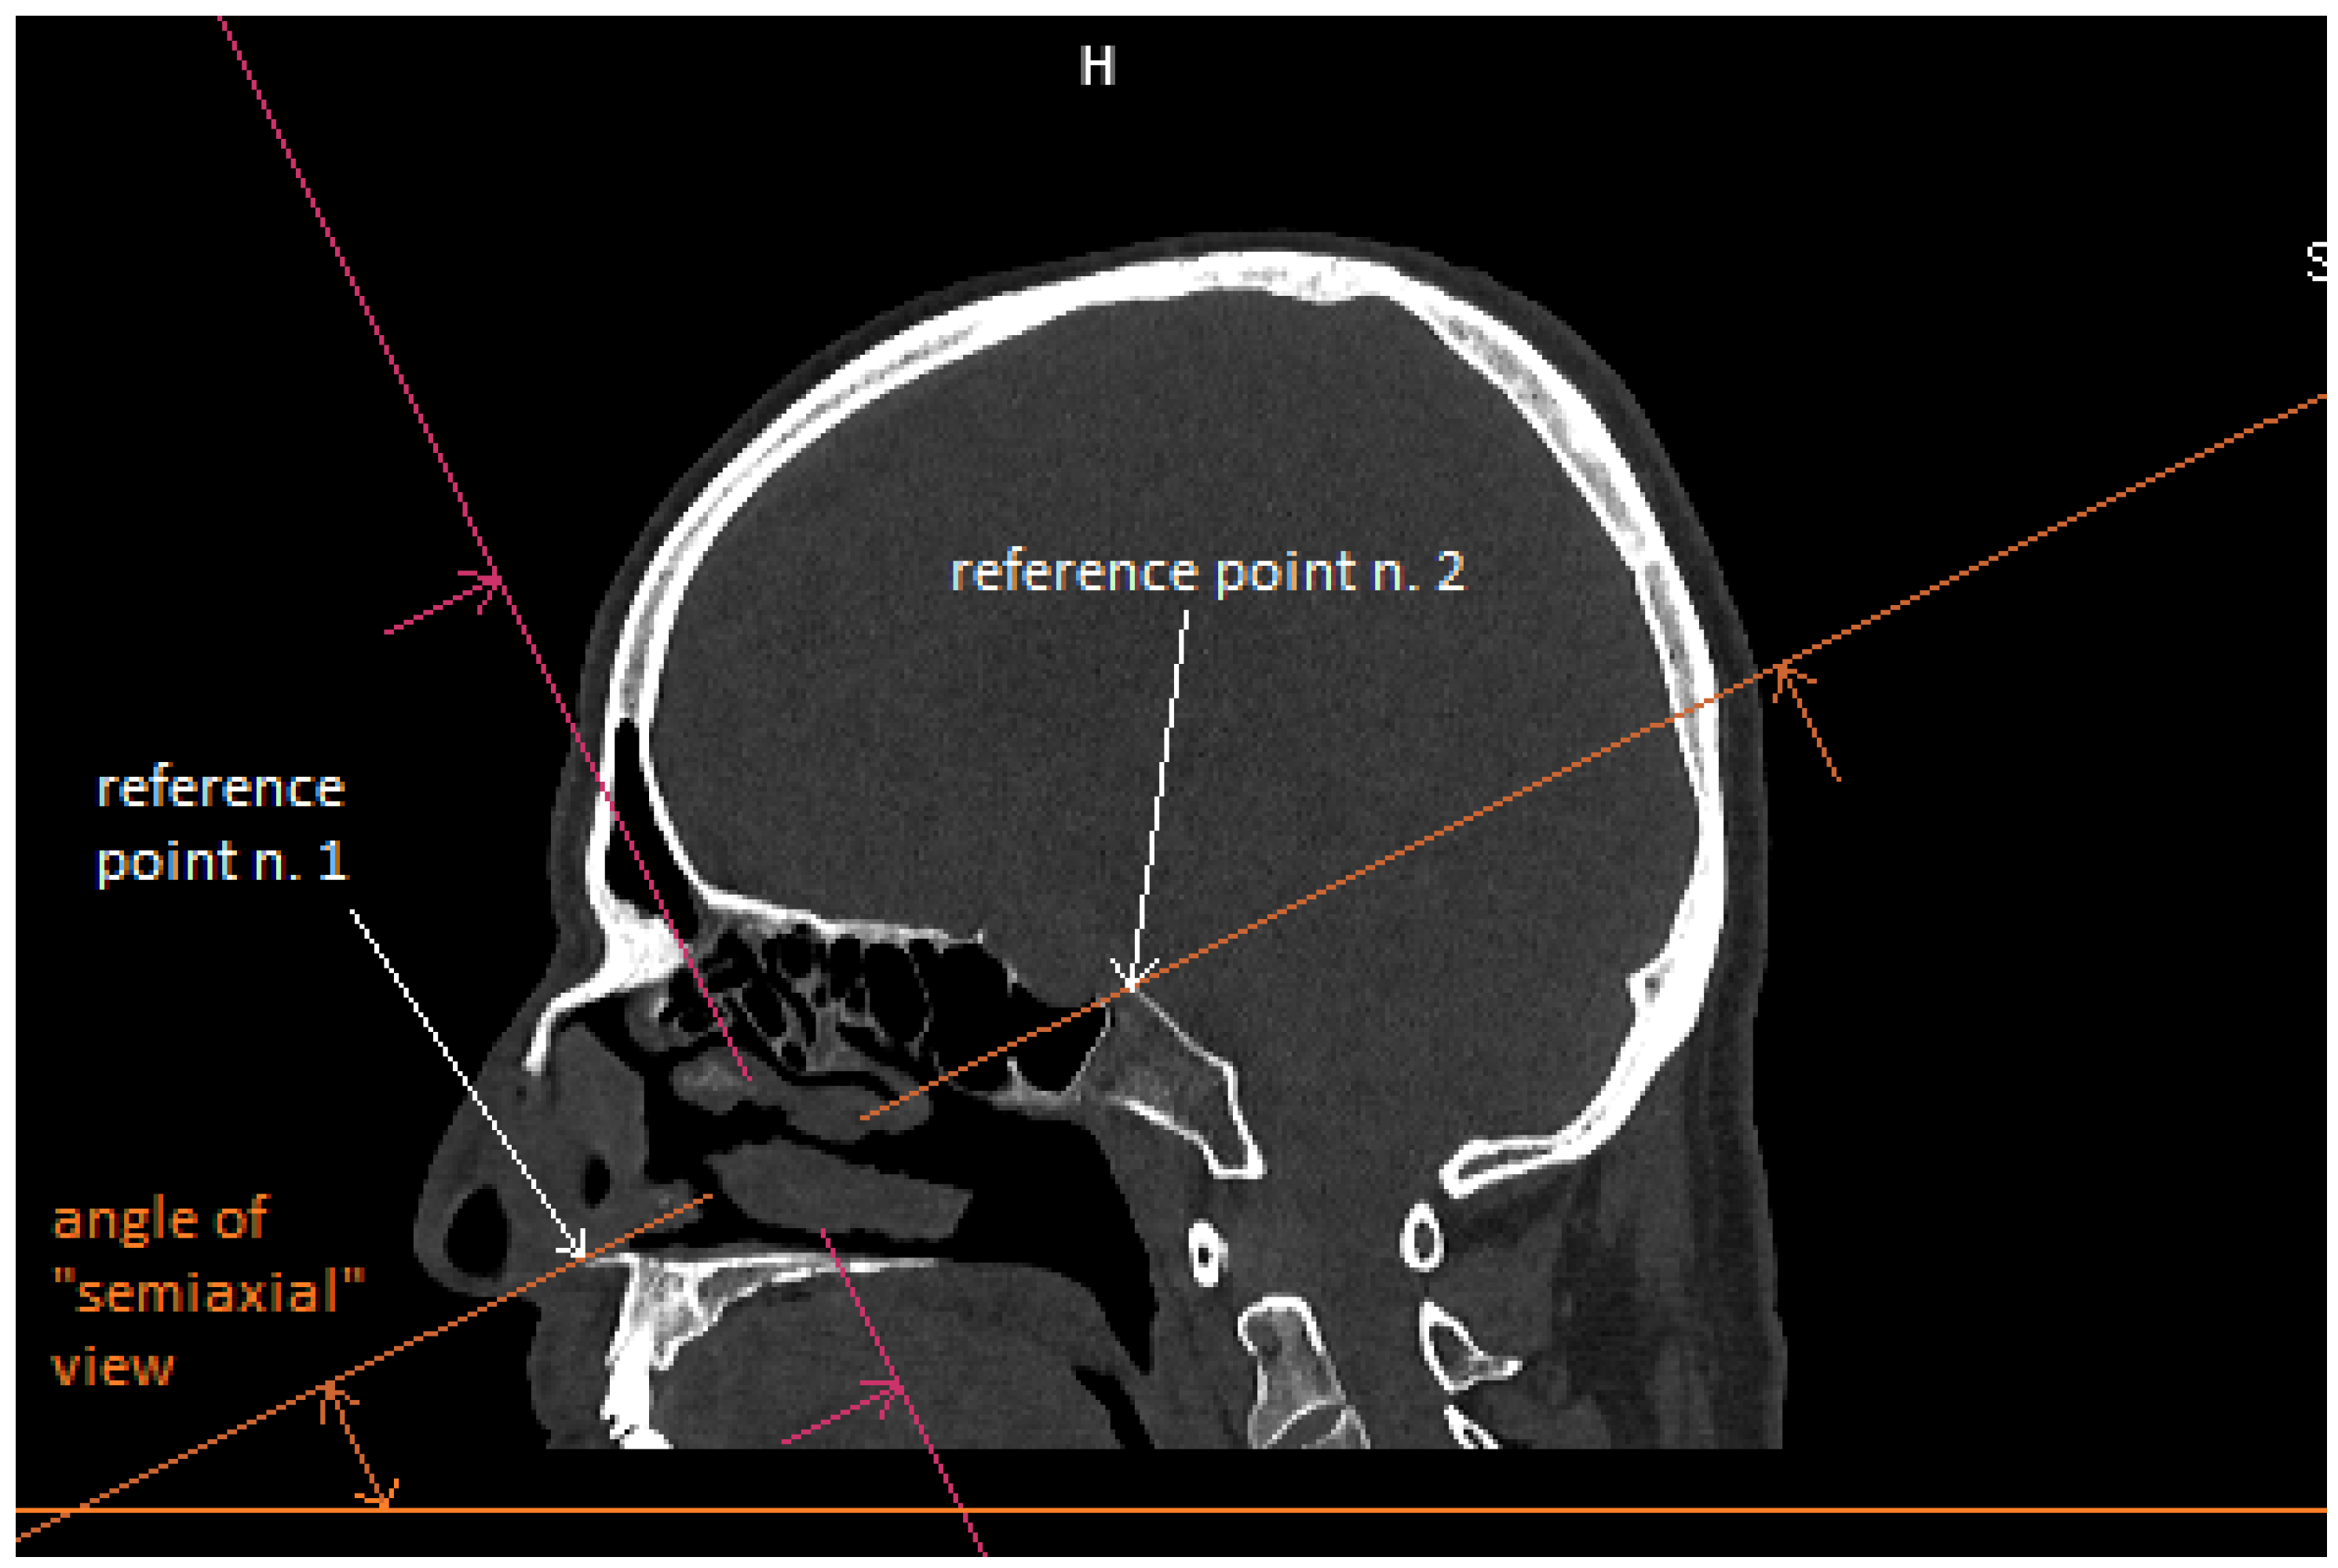

Patient CT scan: Preoperative CT scans from 20 patients with a pituitary adenoma were used for this study. The CT scans were performed on a Siemens Somatom force scanner (Siemens healthineers, Praha, Czech Republic). The measurement was performed with the SyngoVia program, using HrCT images with a slice thickness of 0.6 mm. In each patient, the semi-axial plane was created using multiplanar reconstruction by changing the angle of the axial plane to match the virtual insertion of a straight instrument during surgery through the left nasal cavity into the sphenoid cavity. The defined points for this semi-axial plane were spina nasalis anterior and dorsum sellae (Figure 1). In this semi-axial plane, at the height of the dorsum sellae, the following diameters were measured: the depth of the sphenoid cavity, the distance between the medial edges of the internal carotid arteries (ICA), the width of the pyriform aperture, and the width of the nasal cavity at the level of the attachments of the lower turbinates. The volume of the sphenoid cavity was measured with Fotom software (FOTOM 08 Plus, Ostrava, Czech Republic). Simulation of the virtual insertion of the two straight suctions (one in each nostril) was conducted in a semi-axial view at the height of the dorsum sellae. Instruments were represented with a straight white line; defined points for this white line were the lateral bony edge of the nasal aperture and the medial edge of the ICA. The intersection of the embedded virtual straight instruments (white lines) was marked with a yellow cross. The minimum septal resection required to reach the medial border of the ICA with a straightforward instrument was determined as the distance between the marked yellow cross and the anterior wall of the sphenoid cavity (Figure 2).

Figure 1. CT scan, sagittal view, creation of semiaxial plane (orange line), reference point n. 1–spina nasalis anterior; reference point n. 2–dorsum sellae.